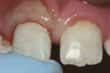

Dente scheggiato - Se non avvertite dolore e la scheggiatura è piccola sta a voi decidere se e quando far riparare il dente. A seconda della grandezza della scheggiatura, il dente può essere lisciato o corretto esteriormente. In alternativa si può ricorrerre a vernici apposite, capsule o otturazioni. Un'otturazione o un dente artificiale scheggiati devono essere sostituiti. Rivolgetevi al vostro dentista per farvi consigliare la soluzione migliore per voi.

dente frontale scheggiato